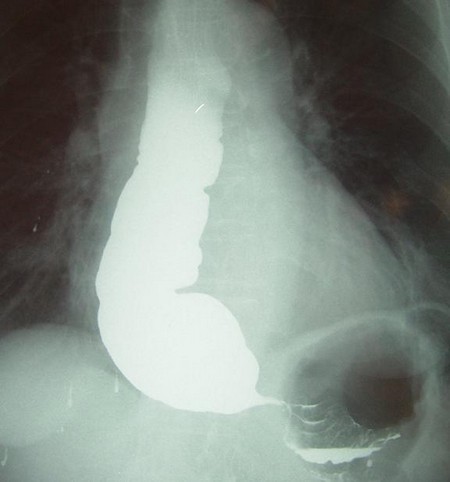

- рентгенологическое контрастное исследование – пациенту предлагают проглотить порцию контрастного вещества (сульфата бария), после этого делают серию рентгенологических снимков. По ним выявляют скорость перемещения сульфата бария по пищеводу и освобождения от него конечного участка пищевода;

При обнаружении указанных симптомов следует немедленно обратиться к врачу. Уточнить диагноз позволяет проведение рентгенологического обследования пищевода с сульфатом бария, фиброэзофагогастроскопии, манометрии пищевода и другие по усмотрению лечащего врача.   Для исключения ишемической болезни сердца (стенокардии) проводят электрокардиографию.

- Рентгенография грудной клетки. Обследование начинается именно с данного исследования. В случае выявления на рентгенограмме тени расширенного пищевода с жидкостным уровнем назначается рентгенография пищевода, предполагающая предварительный прием бариевой взвеси. Если имеет место ахалазия кардии, то становится заметным сужение конечного отдела пищевода, а также расширение участка, располагающегося выше.

Основным критерием эффективности медикаментозного лечения является устранение симптоматики. Для определения эффекта опытным путем проводят рентгенологическое исследование с параллельным введением бария. Если бариевые взвеси нормально проходят по пищеводу, значит, лечение помогло.